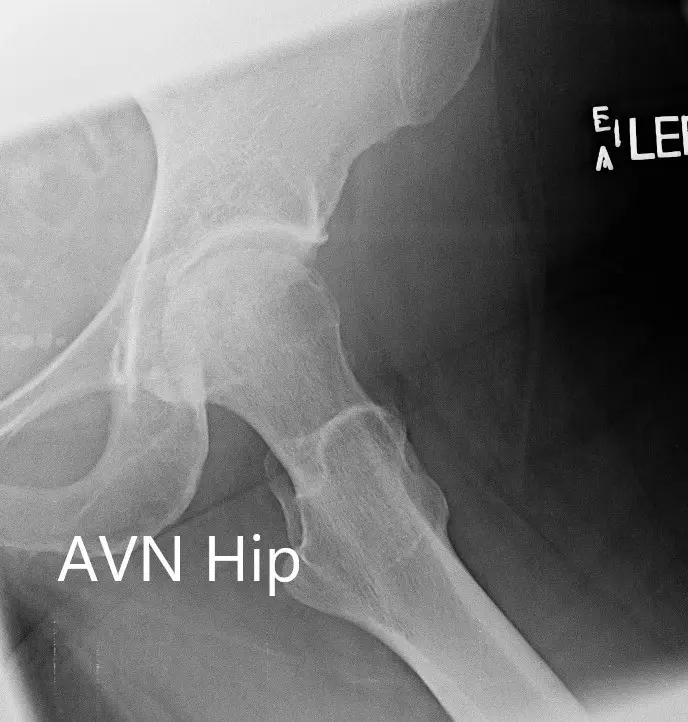

Imaging revealed osteoarthritic changes of the left hip with an AVN lesion that involves 60% of the femoral head. An MRI was obtained which revealed left femoral head avascular necrosis without overt subchondral collapse.

X-ray showing the AP and frog-legged lateral views of the left hip joint